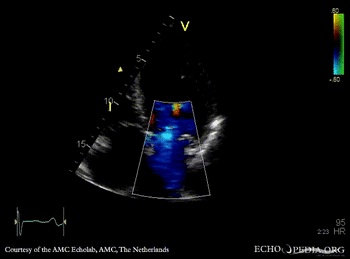

PLAX: Color Doppler, severe mitral regurgitation, excentric jet A4CH: thickend PMVL, prolaps of PMVL